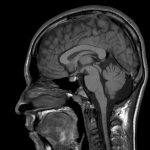

Giải Phẫu MRI Sọ Não | Bài giảng CĐHA

Hình ảnh giải phẫu MRI sọ não.

Axial / Coronal / Sagittal